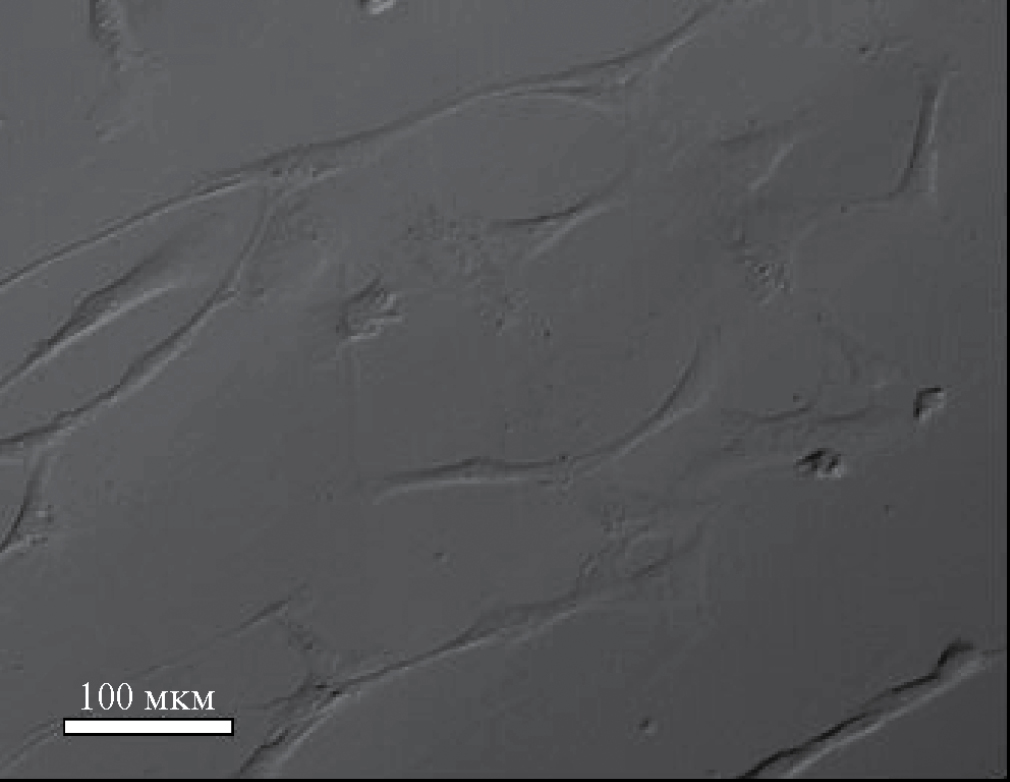

На рис. 5 приведена фотография (оптическая микроскопия) МСК на адгезивной поверхности чашек Петри в невысушенном состоянии.

Рис. 5. Общий вид культуры мезенхимальных стромальных клеток человека на культуральном пластике.

Как следует из рис. 5, МСК клетки сильно вытянуты в длину и имеют размеры примерно 100×10 мкм. То есть вся зона АСМ скана примерно соответствует поверхности одной клетки, а наблюдаемый рельеф – это отдельные частицы в форме агломератов. Из этих данных следует, что частицы в основном находятся на поверхности клеток в виде агломератов, но при этом агломераты оказываются прочно связаны с клеткой, поскольку они не смываются с ее поверхности. Резюмируя часть структурных исследований, можно отметить, что, хотя и косвенно, экспериментальные данные подтверждают предположение о наличии взаимодействия между МНЧ и МСК, в результате которого, по крайней мере, часть МНЧ закрепляется клеточной культурой.